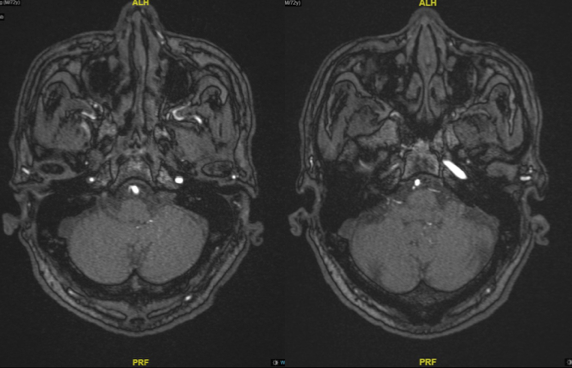

图4 TOF像显示岩骨段慢血流

图5 眼段可见正常管腔,血管负性重构

图6 M1段血管存在